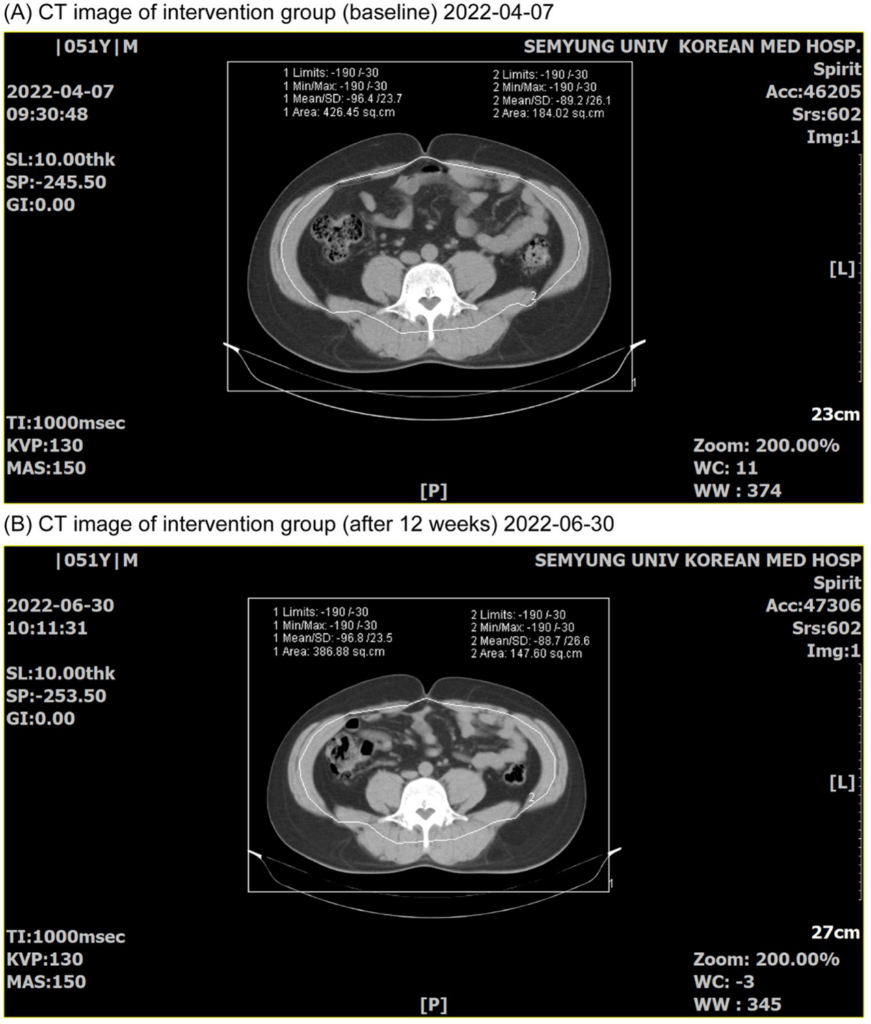

3. 內臟脂肪與腹部脂肪下降更明顯

這篇研究最值得注意的地方,就是它不只是減到表層脂肪,還包括了腹部脂肪區域。

CT 測量結果顯示,黑薑組相較安慰劑組,有更明顯下降:

- 總脂肪面積

- 皮下脂肪面積

- 內臟脂肪面積

- 內臟/皮下脂肪比值

這很重要,因為很多人最想處理的,其實不是四肢,而是肚子、腰間肉、腹部脂肪堆積。而內臟脂肪又和代謝健康、胰島素敏感度、心血管風險有更密切的關係。